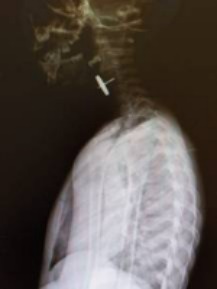

В ведомстве рассказали, что ребёнок играл с машинкой и, заметив, что от неё отвалилось колёсико, проглотил его. Деталь застряла в верхней трети пищевода. Родители быстро среагировали и вызвали медиков. Те, оценив все риски для здоровья ребёнка, приняли решение о срочной транспортировке малыша в Благовещенск.

— Инородное тело, застрявшее в пищеводе, представляло собой металлическую конструкцию на штыре до 1,5 сантиметра в длину с маятником округлой формы до 1,5 сантиметра в диаметре. Инородные тела такой сложной конфигурации опасны перфорацией органов, тканей и сосудов с дальнейшим развитием кровотечения и перитонита и требуют квалифицированной хирургической помощи, – пояснил врач Амурской областной детской клинической больницы.